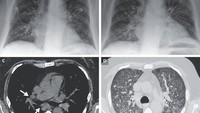

Pasien pertama mengeluhkan mual, muntah, rasa haus berlebihan, ketidaknyamanan perut, nyeri punggung, dan demam. Dokter menemukan cairan menumpuk di paru-parunya yang membuatnya bernapas dengan cepat dan kadar oksigen yang menurun. (Foto: New England Journal of Medicine)